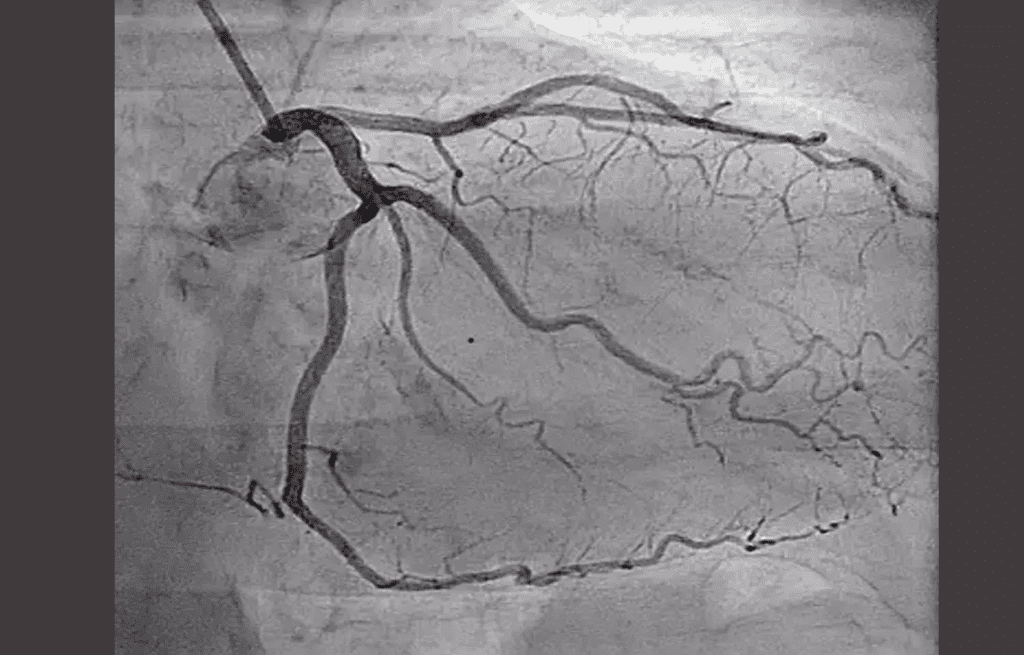

Myocardial perfusion imaging with SPECT is key in finding coronary artery disease. It’s a non-invasive way to see how blood flows and the heart works. It helps spot areas that are not getting enough blood.

Principles of Cardiac Perfusion SPECT

Cardiac perfusion SPECT uses a tiny amount of radioactive tracer. This tracer goes to the heart muscle based on blood flow. A SPECT camera takes pictures from different sides, making 3D images of the heart’s blood flow.

This method works by how the heart takes in the tracer at rest and under stress. If the heart takes in less tracer when stressed, it might be ischemic. If it takes in less at rest too, it might be infarcted.

Cardiac perfusion SPECT gives important info on heart blood flow. It helps doctors decide on treatments and care for heart disease patients.